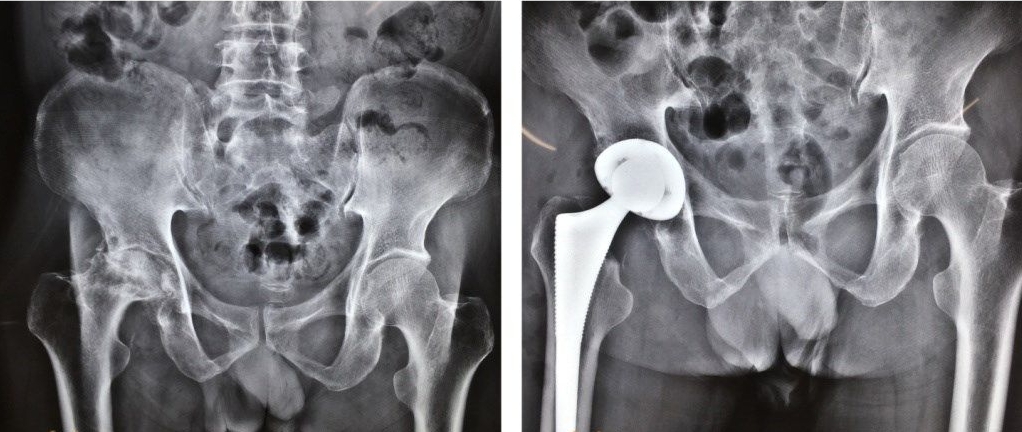

Total hip/knee arthroplasty is the most effective treatment for severe joint diseases. As a mature therapy widely used globally, it is hailed as a key milestone in 20th-century orthopedic development.